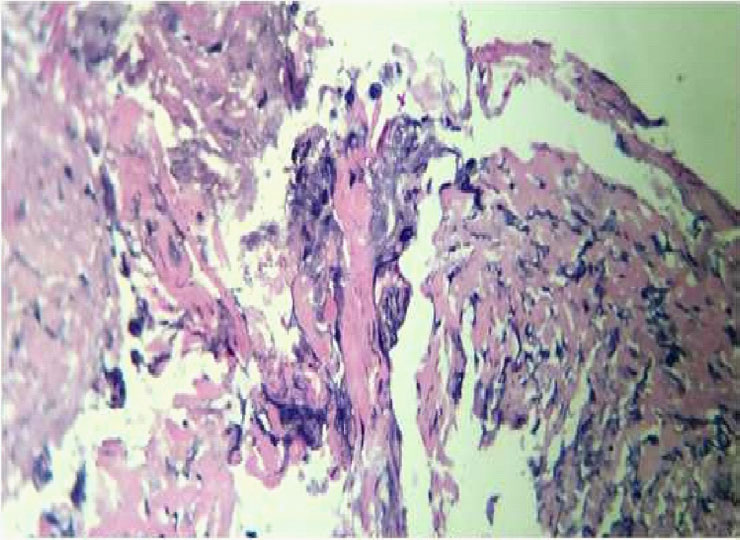

There was a 1 X 1 cm perforation at the gastrojejunostomy (GJ) anastomotic site (Figure 2 and 3). Multiple omento-enteric adhesions were present. Methylene blue test revealed a leak present at the GJ site. Primary closure of defect done after freshening of the edges and an omental patch repair was done. Ulcer edges were sent for histopathological examination (HPE) which showed infectious etiology with candida & actinomyces seen (Figure 4 and 5). Patient was given fluconazole 400 mg intravenously twice daily initially and later switched on to oral tablets for 2 weeks.

Figure 5:Gomori methenamine silver stain

Candida albicans is the most common cause of fungal sepsis, representing 35% to 60% of isolates. GI leakage after bariatric surgery has been identified as an independent risk factor associated with perioperative death [4]. Gastrographin upper GI series examinations are helpful to determine leaks at the gastro-jejunostomy or upper gastric pouch staple line. However, they cannot definitively rule out leaks in other locations. Although abdominal CT scan was positive in this case important limitations exist in its use and accuracy [5,6]. A positive imaging finding should not be awaited before exploring patients in whom the diagnosis is still unclear. In many studies, percutaneous drainage was very helpful in the control of leaks after bariatric surgery [7]. Isolated candida species exhibit varying levels of susceptibility to antifungal drugs. Histopathologic examination remains one of the major diagnostic tools because it permitsrapid, presumptive identification of fungal infections [8].

Histopathologic examination remains one among the main diagnostic tools in mycology because it permits rapid, presumptive identification of fungal infections, even when blood cultures are negative. There are several methods of managing anastamotic leaks, depending on the magnitude of the collection and the clinical presentation. Patients who present early with tachycardia and unilateral decrease in breath sounds warrant an exploratory laparoscopy inspite of a negative contrast test.